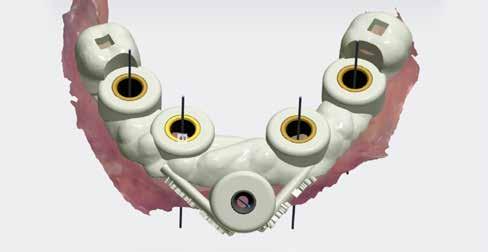

10–13. kép: 3D fúrósablon tervezés 3shape Implant Studio szoftverrel. Implantátum tervezés a 3shape Implant Studio szoftverrel – Négy BioHorizons implantátum vezetőcsappal a 3D nyomtatott sebészeti fúrósablon stabilitásának megőrzéséhez (9. kép). Ezután történt a fúrósablon tervezése a 3shape Implant Studio szoftverrel. Felhasználtuk a megtartott hátsó koronákat, továbbá az anterior területre pozicionált vezető csapot a sablon trapéz alakú stabilitásának kialakításához, mely szükséges a műtét alatt a szájban. Ez a stabilitás elengedhetetlen a húzást követő azonnali eljárás során, teljes állcsontok esetén (10-13. kép).

Ezután egy azonnali ideiglenes hidat készítettünk elfordulásgátló-mentes, ideiglenes bázisokra (23-24. kép). A kezelési terv az volt, hogy PMMA-ból készítjük a hídvázat rózsaszín kompozittal és festéssel kiegészítve.

Megkezdődött a CAD dizájn kialakítása Bradley Grobler fogtechnikai kerámiás szakember által. Látható a képen, hogy az összes információt/adatot egy képernyőre vetítve, a fogpótlás tervezése szintén nagyon egyszerű (25. kép).

A virtuális artikulátor használata a 3shape tervező szoftverben biztosítja a laterális és egyéb zavarok kiküszöbölését (26. kép).

Az okklúzió ellenőrzése a virtuális artikulátorban (27. kép). A digitális implantációs fogászat csodája! Jó tervezéssel és a technológia használatával tudtuk megvalósítani a direkt csavarozású fogpótlást. Nem volt szükség multi-unit felépítményekre a csavarlyukak tökéletes eléréséhez (28-29. kép).

23-24. kép: Az ideiglenes híd tervezése.

BioHorizons implantátum könyvtár – digitális fém analógok, vagy 3D nyomtatott analógok. A BioHorizons teljes digitális könyvtárral rendelkezik, amely lehetővé teszi a digitális munkafolyamat egyszerűségét, hogy egymást erősítve működjön együtt az implantációs rendszerükkel. Az implantátumos modell-gyártás mindkét lehetőségének megléte egyszerű logisztikát tesz lehetővé a legtöbb forgatókönyv lefedése érdekében (30-31. kép). Mart ideiglenes híd elfordulásgátló-mentes ideiglenes bázisokon. Rózsaszín kompozit, illetve GC Optiglaze alkalmazásával készült a fogpótlás (32-35. kép). Az illeszkedő felületek mutatják az elfordulásgátló-mentes bázisokat.